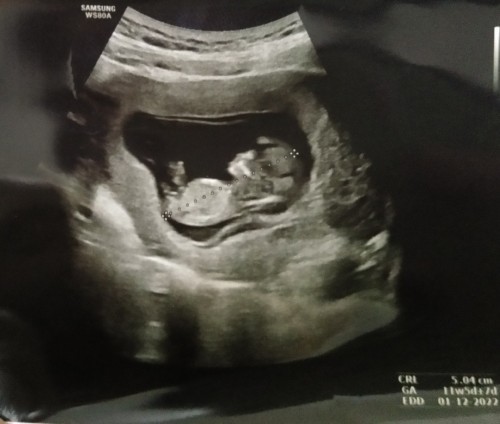

ภาพ ซาวตอน5เดือน มีใครเหมือนบ้านนี้มั้ยคะ ในถาพน้องจะท้องใหญ่ แต่คุณหมอไม่ได้แต้งอะไรค่ะ เป็นปกติมั้ยคะ มีอม่ๆคนไหนเป็นเหมือนกันบ้างคะ

4 เดือนครึ่งค่ะ

11w5d ค่ะ